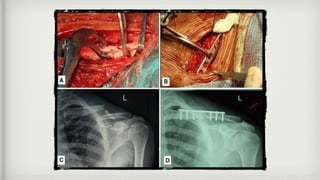

Surgical procedure

• It includes

• Internal fixation with plates and screws

• Intramedullary fixation

Surgical procedure • Itincludes • Internal fixation with plates and screws • Intramedullary fixation • The routine removal of metal work was recommended for IM nails but not for plate fixation in mid-shaft displaced fracture. • In displaced lateral clavicle fracture routine removal of metalwork was performed for • Hook plate fixation • Screw fixation • Cerclage wire fixation • Tension band wire fixation • Not performed for, • Non ACJ spanning plate fixation • Suture fixation • These fixation methods are necessary for lateral clavicle fracture as it involves acromioclavicular joint and various ligaments that may become injured during fracture.